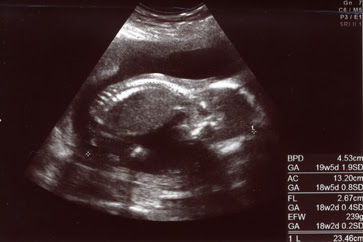

妊娠18週目 18w0d 6d のエコー写真とエピソード 妊娠5ヶ月 Cozre コズレ 子育てマガジン

妊娠18週0日 18w0d の超音波 エコー 写真

妊娠18週目エコー写真 赤ちゃんの大きさ 胎動が分かる人も 妊娠中期 All About

医師監修 妊娠18週のエコー写真 胎動を感じ始めるころ マイナビ子育て

医師監修 妊娠18週のエコー写真を多数掲載 みんなのエピソードつき Michill ミチル

18週0日 Milkywaystさん 25歳 18週0日のエコー写真 Crl 頭殿長 身長 体重 Bpd 頭の横幅 初めて4dのエコーを見る日 お顔が見える 感動 手と足がずっとお顔の前に会って30分の検診中でやっと見ることが出来たお顔の写真